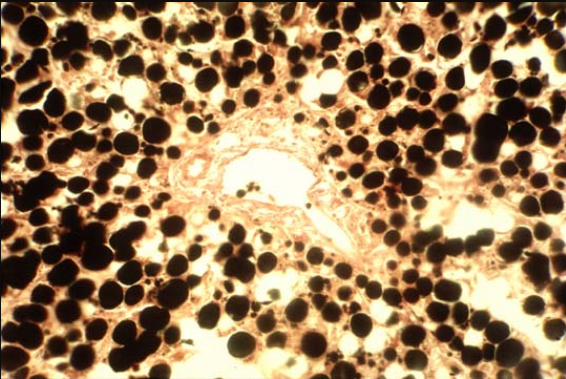

脂滴(Lipid Droplet)是中性脂(主要為甘油三酯和酯化膽固醇)的主要貯存場所,是脂肪細胞的主要成分。正常情況下,除脂肪細胞以外,常規(guī)細胞胞質內不見或僅能看到微量脂滴。

在病理情況下,心、肝、腎等實質器官容易發(fā)生脂肪異常堆積,胞質出現(xiàn)脂滴或者脂滴明顯增多以及形成斑塊等現(xiàn)象。因此,通過脂類染色能將這些脂滴清晰的顯現(xiàn)出來,為病理診斷提供圖像參考。

特殊石蠟切片染色法:由于脂肪易溶于有機溶劑,所以不能直接乙醇脫水包埋制成石蠟切片進行染色。若是非要制成石蠟切片,需要將初步固定后的組織先浸泡不飽和脂肪酸置換進脂滴,然后置于重金屬酸溶液中固定處理,重金屬酸經(jīng)不飽和脂肪酸的還原作用形成黑色的重金屬——脂質復合物,不會被二甲苯、乙醇等有機溶劑所溶解,對很微小的脂肪滴都能清晰顯示。之后再進行脫水、透明等程序包埋成蠟塊,切片后經(jīng)脫蠟、透明可直接中性樹膠封片,切片能夠長期保存。但整個過程所需試劑繁雜,整體操作時間較長,且重金屬酸屬于有毒有害物質,所以一般不建議使用本染色方法。